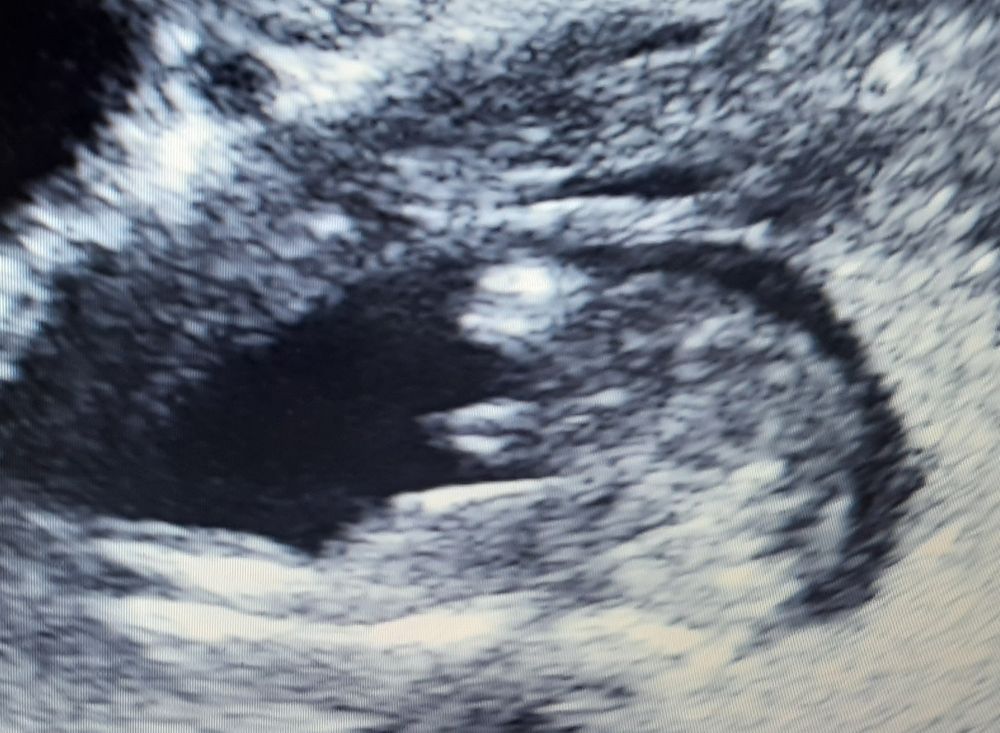

Определение пола в 14/3

Не терпеливо сходили на УЗИ и врач сказал: вон как торчит, точно мальчик.

Но кому ни покажу все говорят, что на девочку похоже. Да, торчит, но форма совсем не мальчиковая.

Скажите, пожалуйста, что видите

У меня точно такая же фотка, врач специально ее сделала, чтобы показать мне , что у нас мальчик

Ну я уж не знаю как вы себе по другому мальчиковые формы представляете))) Тут мужичок у вас во всей красе)))

Мальчик) не понимаю, как вы представляете, чтобы было похоже на мальчика, если это непохоже))

Ну у врача УЗИ, подозреваю, гораздо больше опыта и знаний, чем у тетенек на форуме и тех, у кого вы спрашиваете (если только эти люди не узисты). На девочку не похоже, но я, честно говоря, не помню, с какого срока формируются уже первичные половые признаки вместо полового бугорка и смотрят ли их на таком сроке в таком ракурсе. Дочку мне увидели в 15,3 со 100% уверенностью, и крупным планом показали вполне себе сформированные половые губы.